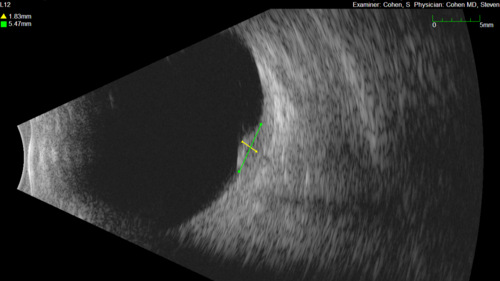

Small choroidal melanoma

28 year old man Serial images suggested that the lesion is growing

OD: sc20/16

OS: sc20/40+2

IOP: TP: OD:19 OS:16